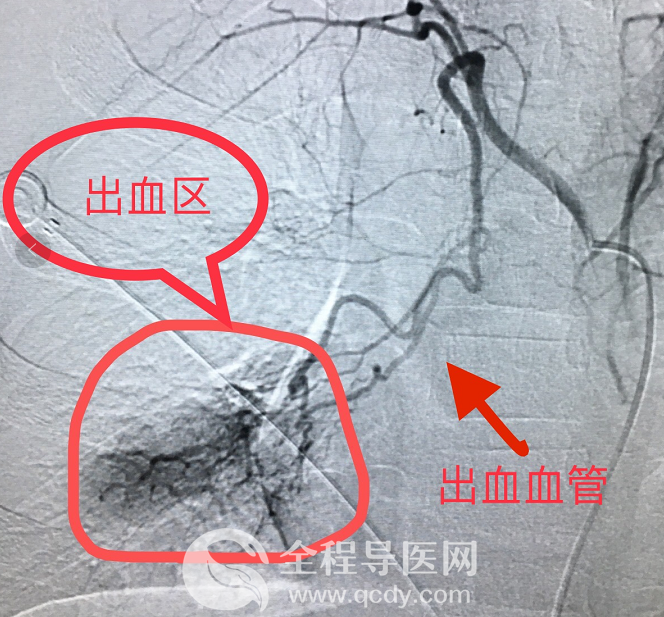

明確治療方案后,經(jīng)過(guò)與患兒家長(zhǎng)詳細(xì)溝通并取得充分信任后,介入科李炯團(tuán)隊(duì)迅速完成手術(shù)相關(guān)準(zhǔn)備,患兒隨即被推進(jìn)介入手術(shù)室。手術(shù)過(guò)程中,患兒持續(xù)輸血、補(bǔ)液、呼吸機(jī)輔助呼吸等,李炯醫(yī)生通過(guò)嫻熟、精細(xì)的血管內(nèi)操作,精準(zhǔn)、快速尋找到血管出血點(diǎn),并注入明膠海綿顆粒以及PVA等栓塞劑,徹底對(duì)出血點(diǎn)進(jìn)行封堵。同時(shí)導(dǎo)管室護(hù)理團(tuán)隊(duì)密切配合,穩(wěn)定患兒生命體征,經(jīng)過(guò)近兩小時(shí)的緊張救治,患兒血色素逐漸上升。術(shù)后行造影證實(shí)出血點(diǎn)已經(jīng)確切止血。

來(lái)醫(yī)院時(shí),由于孩子病情嚴(yán)重,并咳出大量鮮血,樂(lè)樂(lè)被迅速轉(zhuǎn)入重癥醫(yī)學(xué)科,醫(yī)護(hù)人員立即組織MDT多學(xué)科聯(lián)合會(huì)診,并經(jīng)支氣管鏡檢查,孩子肺部出現(xiàn)不少小小的出血點(diǎn),為更加明確出血點(diǎn),通過(guò)增強(qiáng)CTA檢查,發(fā)現(xiàn)樂(lè)樂(lè)肺部有一明顯出血的血管。

情況危急,先行止血,爭(zhēng)取后續(xù)治療時(shí)間。取得患兒家長(zhǎng)充分信任后,介入科團(tuán)隊(duì)快速做好術(shù)前準(zhǔn)備。李炯醫(yī)生在患兒的支氣管動(dòng)脈里面插入一個(gè)很細(xì)的管子,并注入PVA顆粒和明膠海綿顆粒進(jìn)行精準(zhǔn)栓塞,將出血點(diǎn)牢牢堵死,從而使血流不過(guò)去,手術(shù)歷經(jīng)2個(gè)小時(shí)。術(shù)后第二天,孩子恢復(fù)良好,并達(dá)到出院標(biāo)準(zhǔn)。